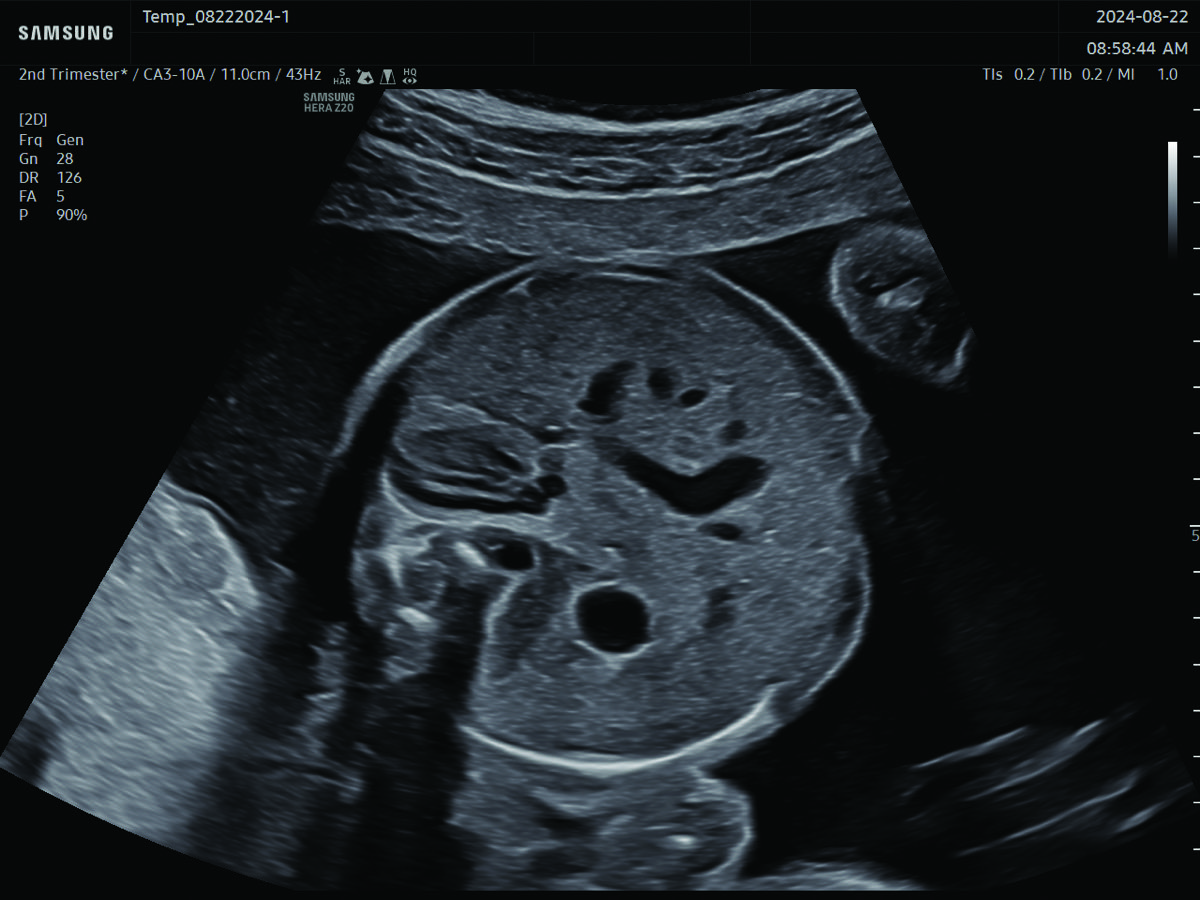

Maternal-Fetal Medicine Consultation

In-depth evaluation of maternal and fetal conditions requiring specialized care such as diabetes, hypertension, thyroid disease, autoimmune disorders, or fetal growth or anatomy concerns.

Comprehensive, advanced and expert MFM care for high-risk pregnancies

- Fetal anomalies